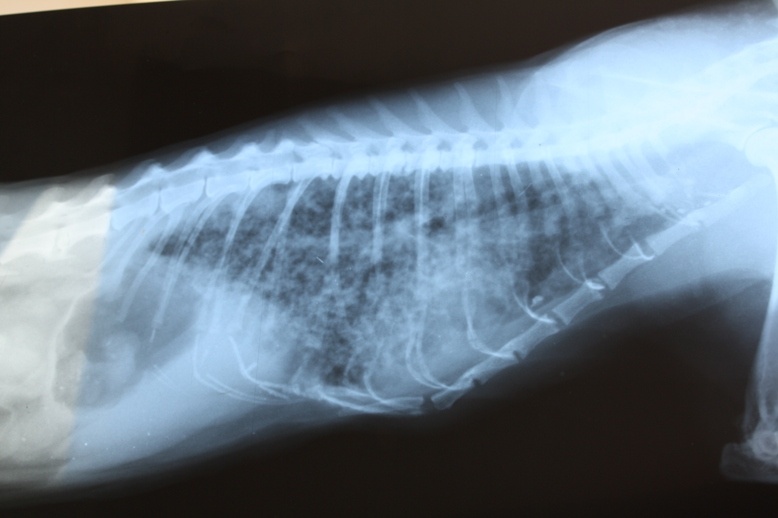

Рентген сегодня показал полное поражение легких - развились метастазы.

С таким поражением легких у нее не было шансов.

Рентген, который мы у тебя нашли, кажется еще я делала - там нет метастаз.

С одной метастазиной наверное у Ольги.

А вот в сравнении: